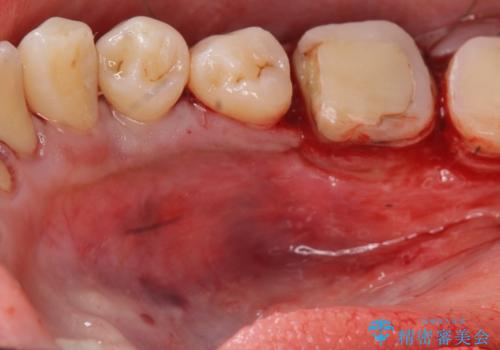

{ 歯周外科 } 骨隆起除去を含む歯冠長延長術

歯周外科を行うことで、歯ぐきの位置を下げ歯の高さを作り出し安定したクラウンの装着が可能となります。また同時に舌の邪魔となっていた骨隆起の除去を行うこととしました。

歯周外科に際しては、静脈内麻酔を行うことでほとんど記憶のないうちにリラックスした状態で受けていただくことができました。